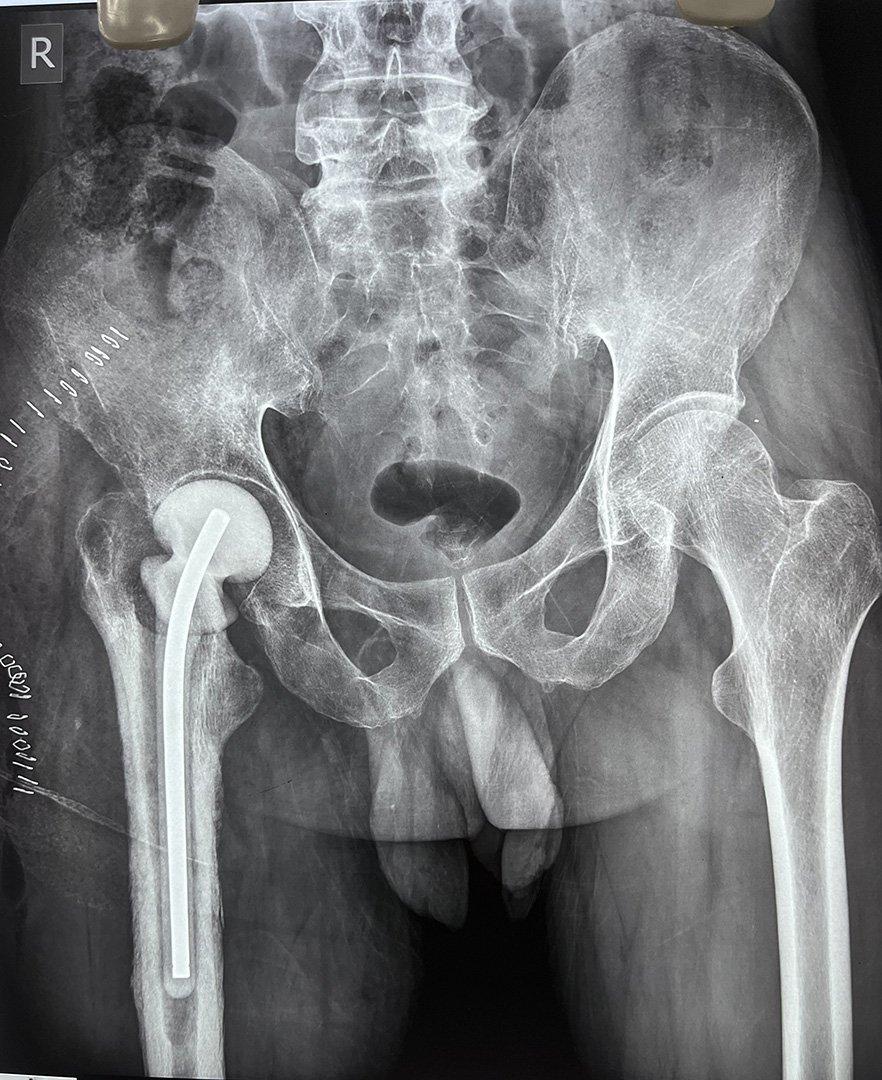

Pre-Op X-Ray